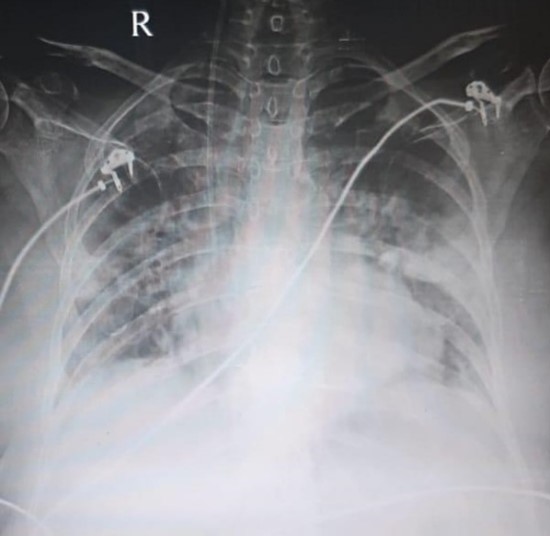

X ray On Discharge